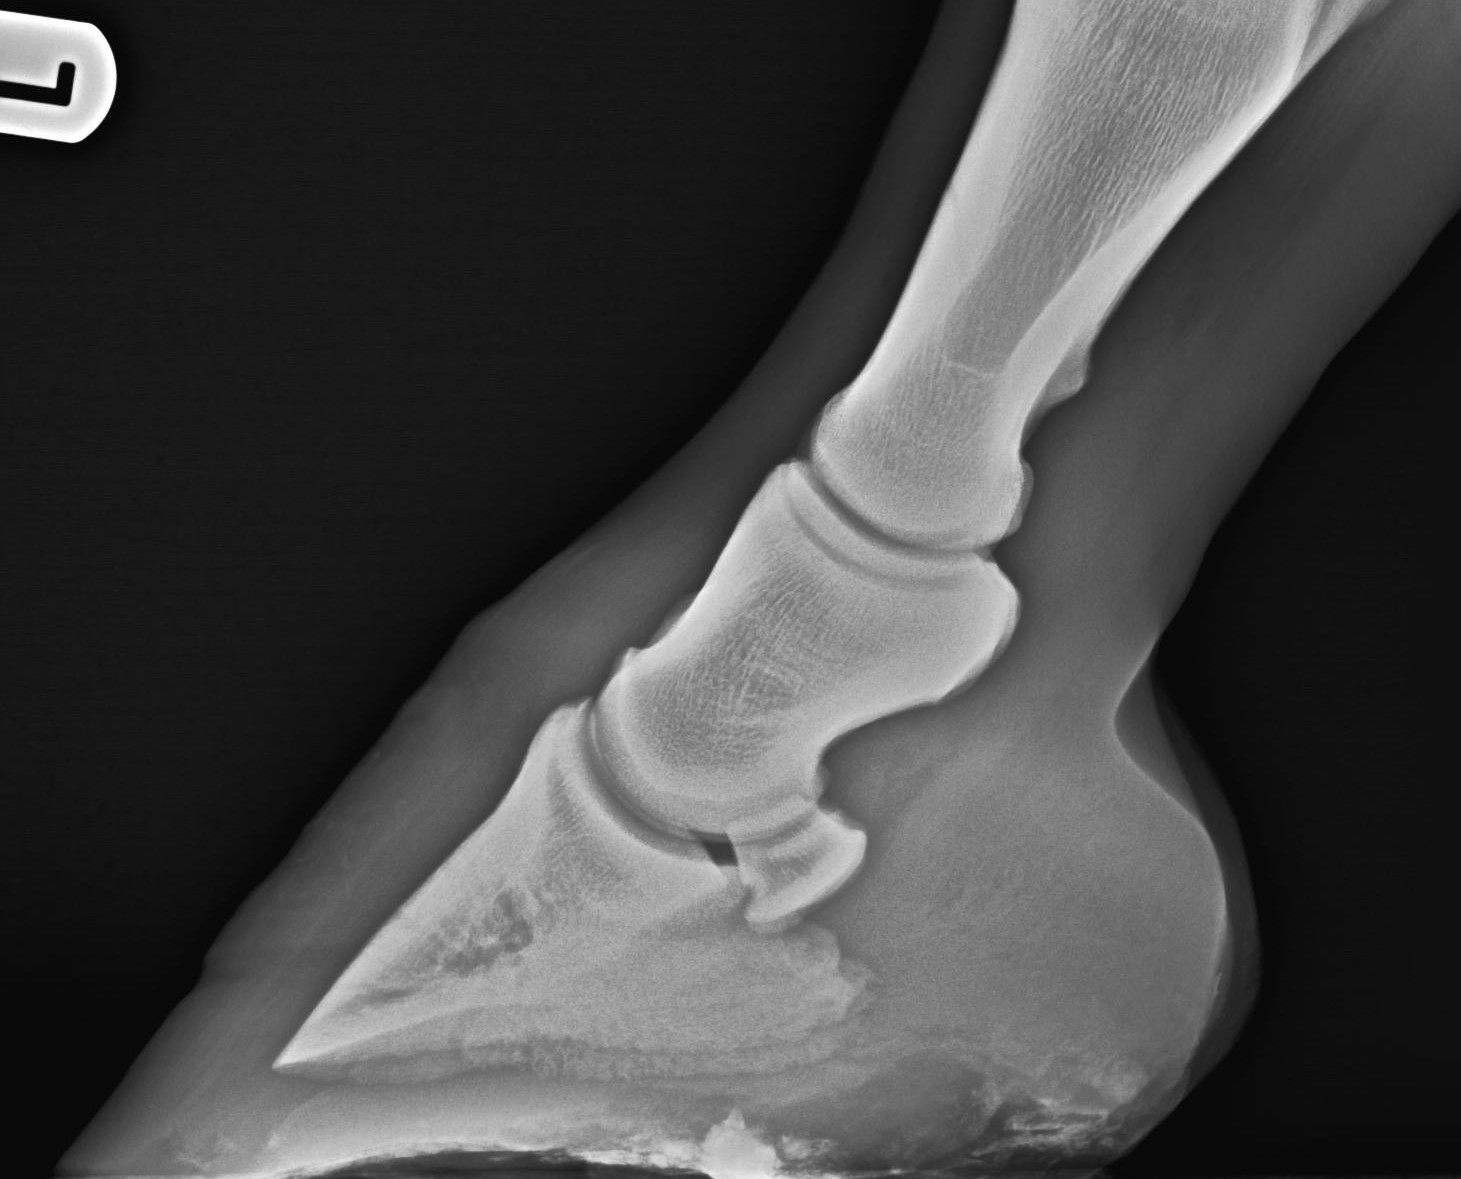

RöntgenZehe